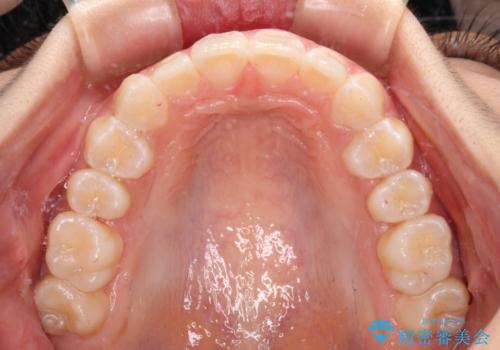

深い咬み合わせで前方に煽られた前歯 高校生のインビザライン矯正治療

- 前歯の隙間と前方に飛び出していることを気にして来院された患者様です。

奥歯の咬み合わせを見ると、上顎が下顎に対して相対的に前方にありました。

咬み合わせも深くなっていたため、上顎臼歯を後方に移動させつつ、下顎の小臼歯を直立させ、奥歯の咬み合わせを改善する必要があります。

奥歯の咬み合わせと深い咬み合わせを改善した後、隙間などをインビザラインで整えることとしました。